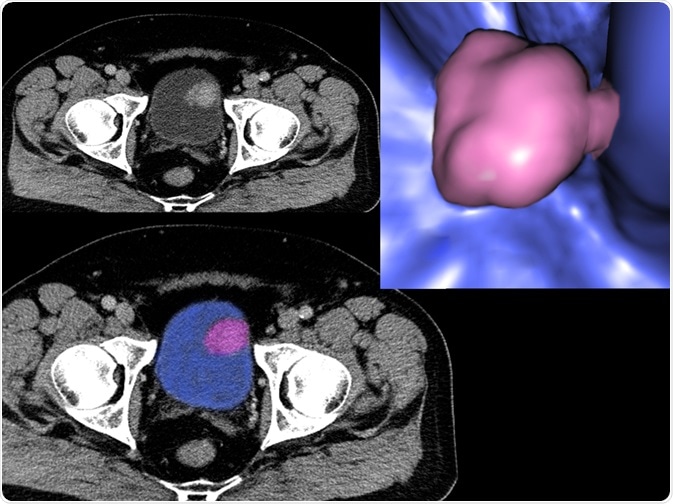

Firstly, a computed tomography (CT) scan can be carried out, which forms a three-dimensional (3D) image of the internal organs of the body using X-rays. More specifically, a CT scan involving the bladder is called a CT urogram. This technique can be used to detect changes in tissue structure and nearby lymph nodes, thus indicating the size and position of the tumor, as well as the stage of the cancer.